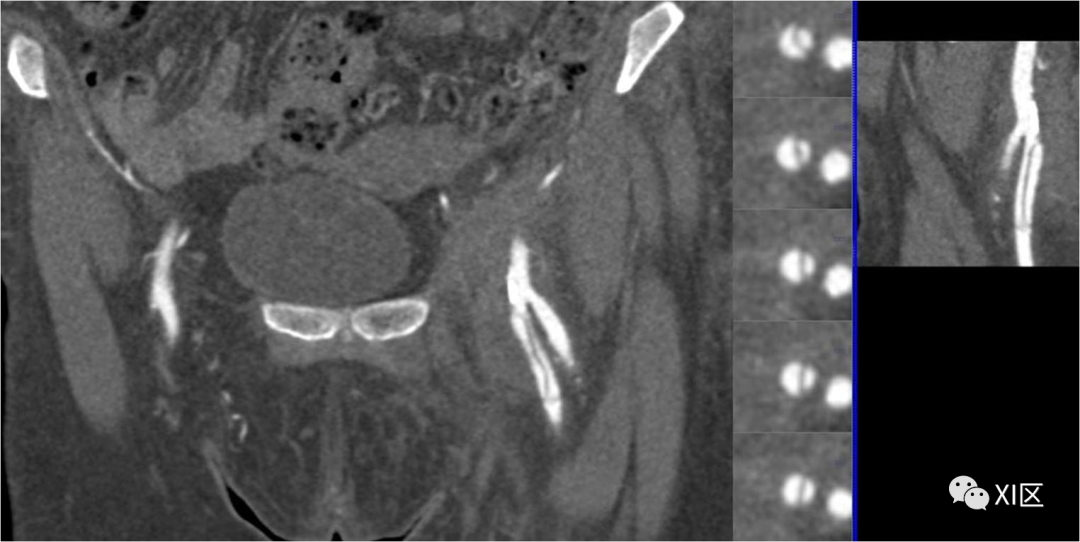

图7 腘窝夹闭综合征。45岁男性,双侧腘窝卡压综合征。大腿(a)和腿(b)冠状位MIP重建。双侧腘动脉未显影(白色箭头),侧枝血管(黑色箭头)清晰可见。

腘动脉夹闭(图7)是指腘动脉与腓肠肌的异常关系,导致动脉受压和跛行,尤其是年轻患者。高达67%的病例存在双侧累及。在临床检查中,主要表现为远端脉搏正常,脚处于中立位置,当脚被迫背屈或跖屈时脉搏消失。